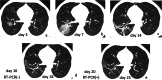

Results: A total of 272 CT scans from 100 patients (mean age, 52.3 years ± 13.1) were investigated. Four patients with lung abnormalities on CT first showed negative RT-PCR result and turned positive afterwards. One hundred sixty-nine (62.1%) showed predominantly peripheral distribution. The CT scores of the upper zone (3.4 ± 3.6) were significantly lower than those of the middle (5.0 ± 3.9) and lower (4.8 ± 3.6) zones (p < 0.001). The CT scores of the anterior zones (4.9 ± 4.7) were significantly lower than those of the posterior zones (8.4 ± 6.2) (p < 0.001). In the early rapid progressive stage (1~7 days), ground glass opacity (GGO) plus reticular pattern (58.1%), GGO plus consolidation (43.0%), and GGO (41.9%) were all common. In the advanced stage (8~14 days), GGO plus consolidation (79.8%) and repairing CT signs (subpleural line, bronchus distortion, and fibrotic strips) showed a significant increase (p < 0.05). In the absorption stage, GGO plus consolidation (9.1%) sharply decreased (p < 0.05).

Conclusion: CT imaging of COVID-19 pneumonia showed a predominantly peripheral, middle and lower, and posterior distribution. The early rapid progressive stage is 1~7 days from symptom onset, the advanced stage with peak levels of abnormalities on CT is 8~14 days, and the abnormalities started to improve after 14 days.

Key points: • The course of COVID-19 pneumonia consists of three stages: 1~7 days is the early rapid progressive stage, 8~14 days is the advanced stage, and after 14 days, the abnormalities started to decrease. • In the early rapid progressive stage, GGO plus a reticular pattern, GGO plus consolidation, and GGO were all common signs; in the advanced stage, signs of progression and absorption coexisted; lung abnormalities showed an asynchronous process with parts with absorption and parts progressing. • Lung abnormalities mainly showed predominantly peripheral, middle, and lower distribution.